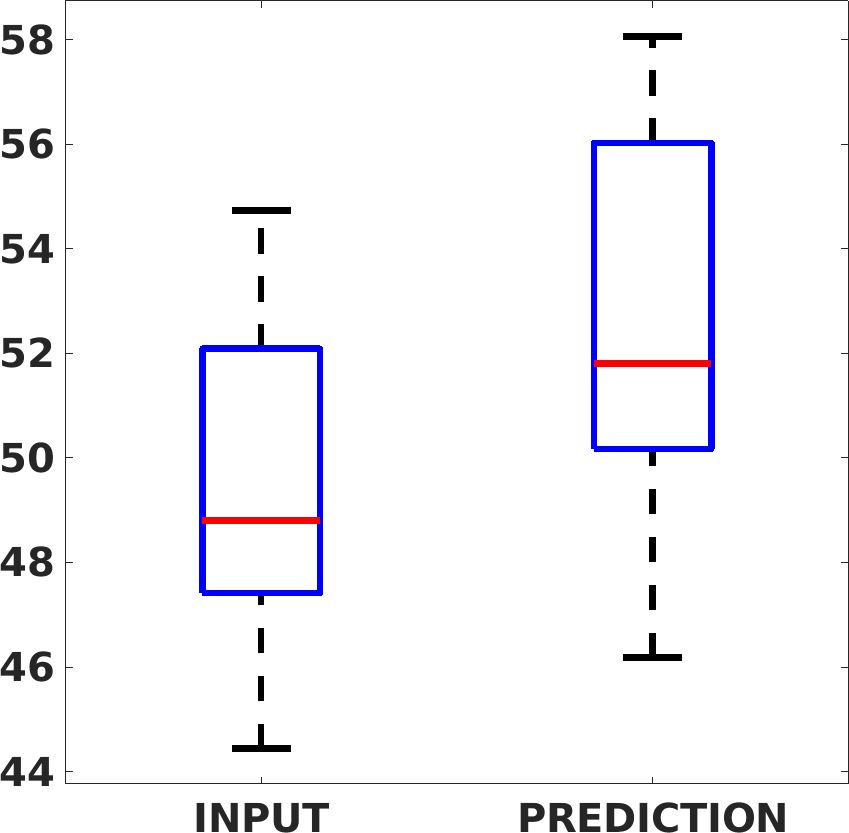

Fig. 7(a-b-c, left) shows the box plot of the statistics of the PSNR on three different anatomical districts, comparing the target images with the prediction and the cubic convolution, respectively. The metrics are computed on a data set of 200 images of the same district and with the same up-sampling factor. We report that the PSNR median value improves of on obstetric 2X raw images, on cardiac 2X raw images, and on abdominal raw 4X images.

Fig. 7(a-b-c, right) shows the histogram of the absolute value of the error with respect to the target image, of the prediction and Cubic convolution results, respectively. The histograms show the number of pixels where the prediction error is lower than 5 (i.e., the first bin of the histogram), which means very similar to the target when visually analysing the images. From the Cubic convolution to the predicted images, this value increases of on obstetric 4X raw images, on cardiac 4X raw images, and on abdominal 4X raw images.

Fig. 17 (left) shows the box plot of the quantitative metrics, comparing the target images with the prediction and the Cubic convolution, respectively. The PSNR metric is computed on a data set of 200 images, belonging to the same district, and with the same up-sampling factor. Analysing the obstetric anatomical district and concerning the corresponding raw images (Fig. 7 (a, left)), the denoising allows the network to significantly improve the results of the up-sampling and the prediction. In particular, comparing the target images with the predicted images, the median PSNR value of obstetric 2X denoised images is 51.8, compared to the median PSNR value of obstetric 2X raw images which is 36.9.